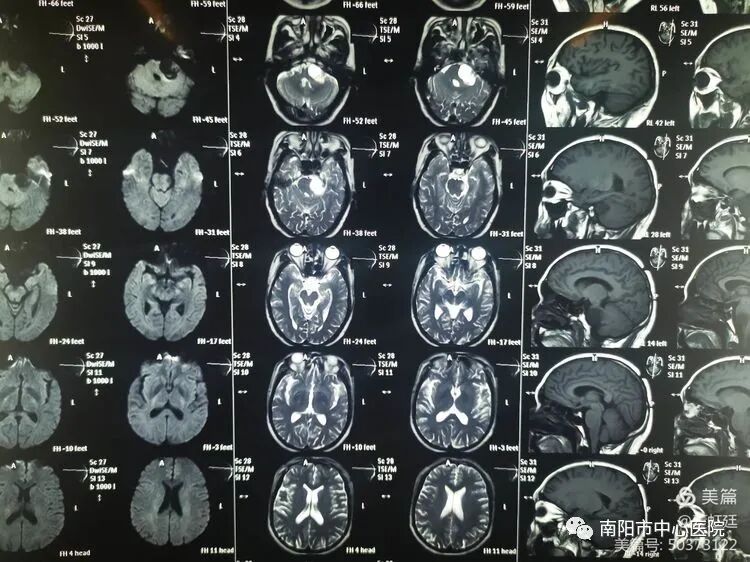

外院頭部MR平掃

患者高某,男,46歲,以“頭暈、耳鳴伴左側(cè)面部麻木2月余”為主訴入院,入院查體,左側(cè)聽力下降,左側(cè)面部感覺減退,余無特殊。結(jié)合外院頭部MR:左側(cè)橋小腦角區(qū)囊實性占位。入院診斷:左側(cè)橋小腦角區(qū)占位,考慮聽神經(jīng)瘤可能性大。